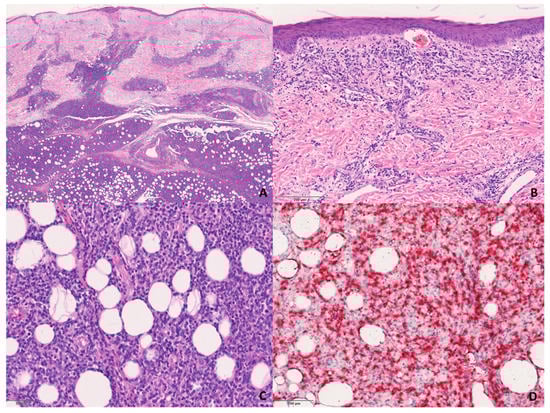

The S-PCGDTCL cases showed the diffuse proliferation of pleomorphic lymphocytes with prominent involvement of subcutaneous tissue and dermis (Figure 3). The infiltrate tended to focally rim adipocytes in some cases, and all but two showed intra-epidermal vesiculation, necrosis, and ulceration.

Figure 3. Histological features of the S-GDTCLs. (A) Dermal and subcutaneous involvement of the infiltrate. H&E, 200×. (B) Detail of the infiltrate in the dermis. H&E, 200×. (C) Detail of the lobular infiltrate of pleomorphic lymphocytes in subcutaneous tissue. H&E, 200×. (D) TCRδ-positive neoplastic cells in subcutaneous tissue. Immunophosphatase, 200×.